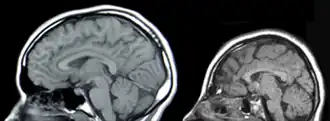

- F7x.x8 — …обусловленная другими уточнёнными причинами (например: врождённая аномалия головного мозга, краниосиностоз, микроцефалия, гипертелоризм и т. д.)